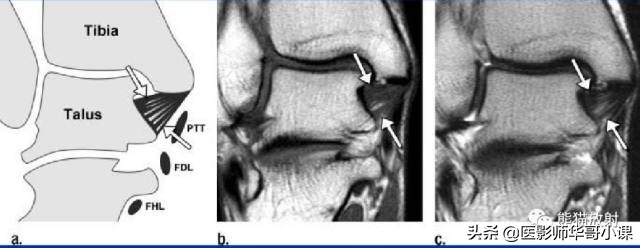

↓ 胫舟韧带

↓ 胫跟韧带

↓ 胫距前韧带

↓ 胫距后韧带

↓ 胫距后韧带损伤